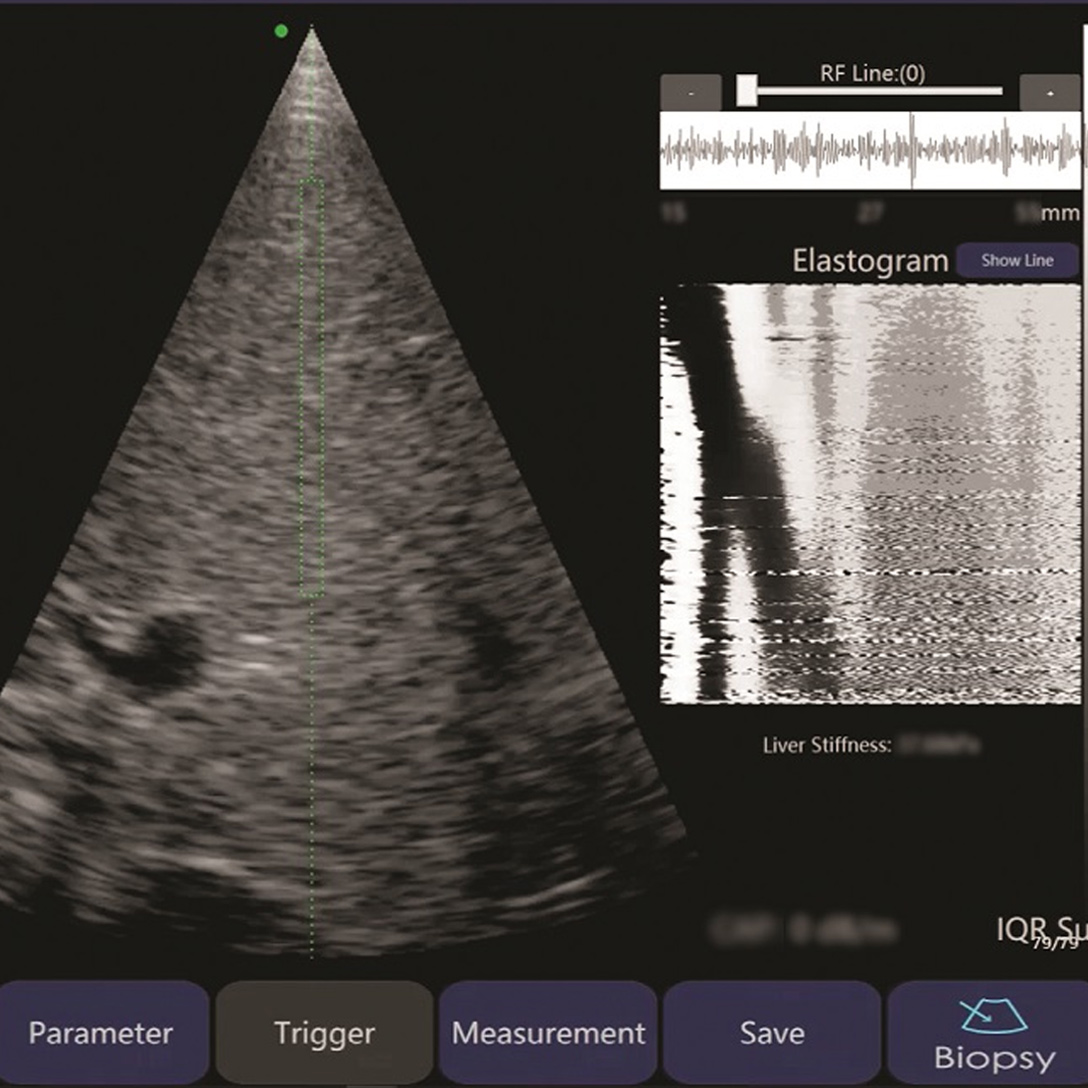

Liverscan配備專利B型超聲波實時影像引導功能,能配合實時影像引導量度肝臟的硬度。這樣,操作人員就像手持地圖一樣,能即時知道應該避開哪些位置,大大提升結果的準確性。

現時市場上的瞬時彈性成像系統大多體積較大,並須安裝在診所或醫院中,且價格高昂。相反,Liverscan把瞬時彈性成像和實時超聲波影像引導系統兩項複雜技術應用在內置無線上網功能的探頭上。操作人員只需在平板電腦上安裝應用程式,然後將探頭連接無線上網,便能開始使用儀器。Liverscan小巧便攜,成本遠低於其它瞬時彈性成像系統。通過降低成本、縮短檢測時間和提升準確度,Liverscan能讓相關診斷程序走進社區,使肝纖維化評估普及化。2021年3月,Liverscan在瑞士日內瓦國際發明展的2021年網上特別展覽中榮獲銀獎。